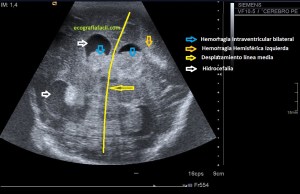

En la imagen 3 ves una imagen de un lipoma, mide 7 cms, la huella de la sonda mide 5cms, la «panoramic view» posee una regla centimetrada que sigue el contorno de la imagen, justo en la profundidad de la misma y lo marca la flecha amarilla. La profundidad la marca la flecha roja y la flecha blanca marca el rango centimetral de los 5cms, fíjate que la línea blanca es ligeramente mayor cada 5 cms. Sirve de referencia, como en la imagen 4 donde ves una colección en el glúteo de más de 10 cms.